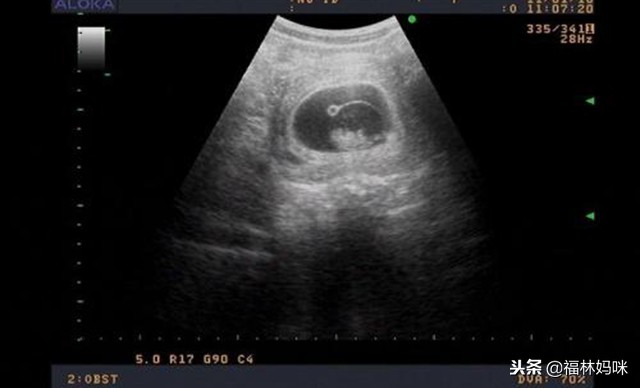

另外,孕酮低的孕妈可以多吃一些如大豆、柚子、草莓、猕猴桃等能够补充天然黄体酮的食物,尽量卧床休息,并且要记得按时到医院去检查,关注孕酮指数,以及胎芽发育情况,等到顺利进入四个月之后,孕妈们就可以松一口气了。